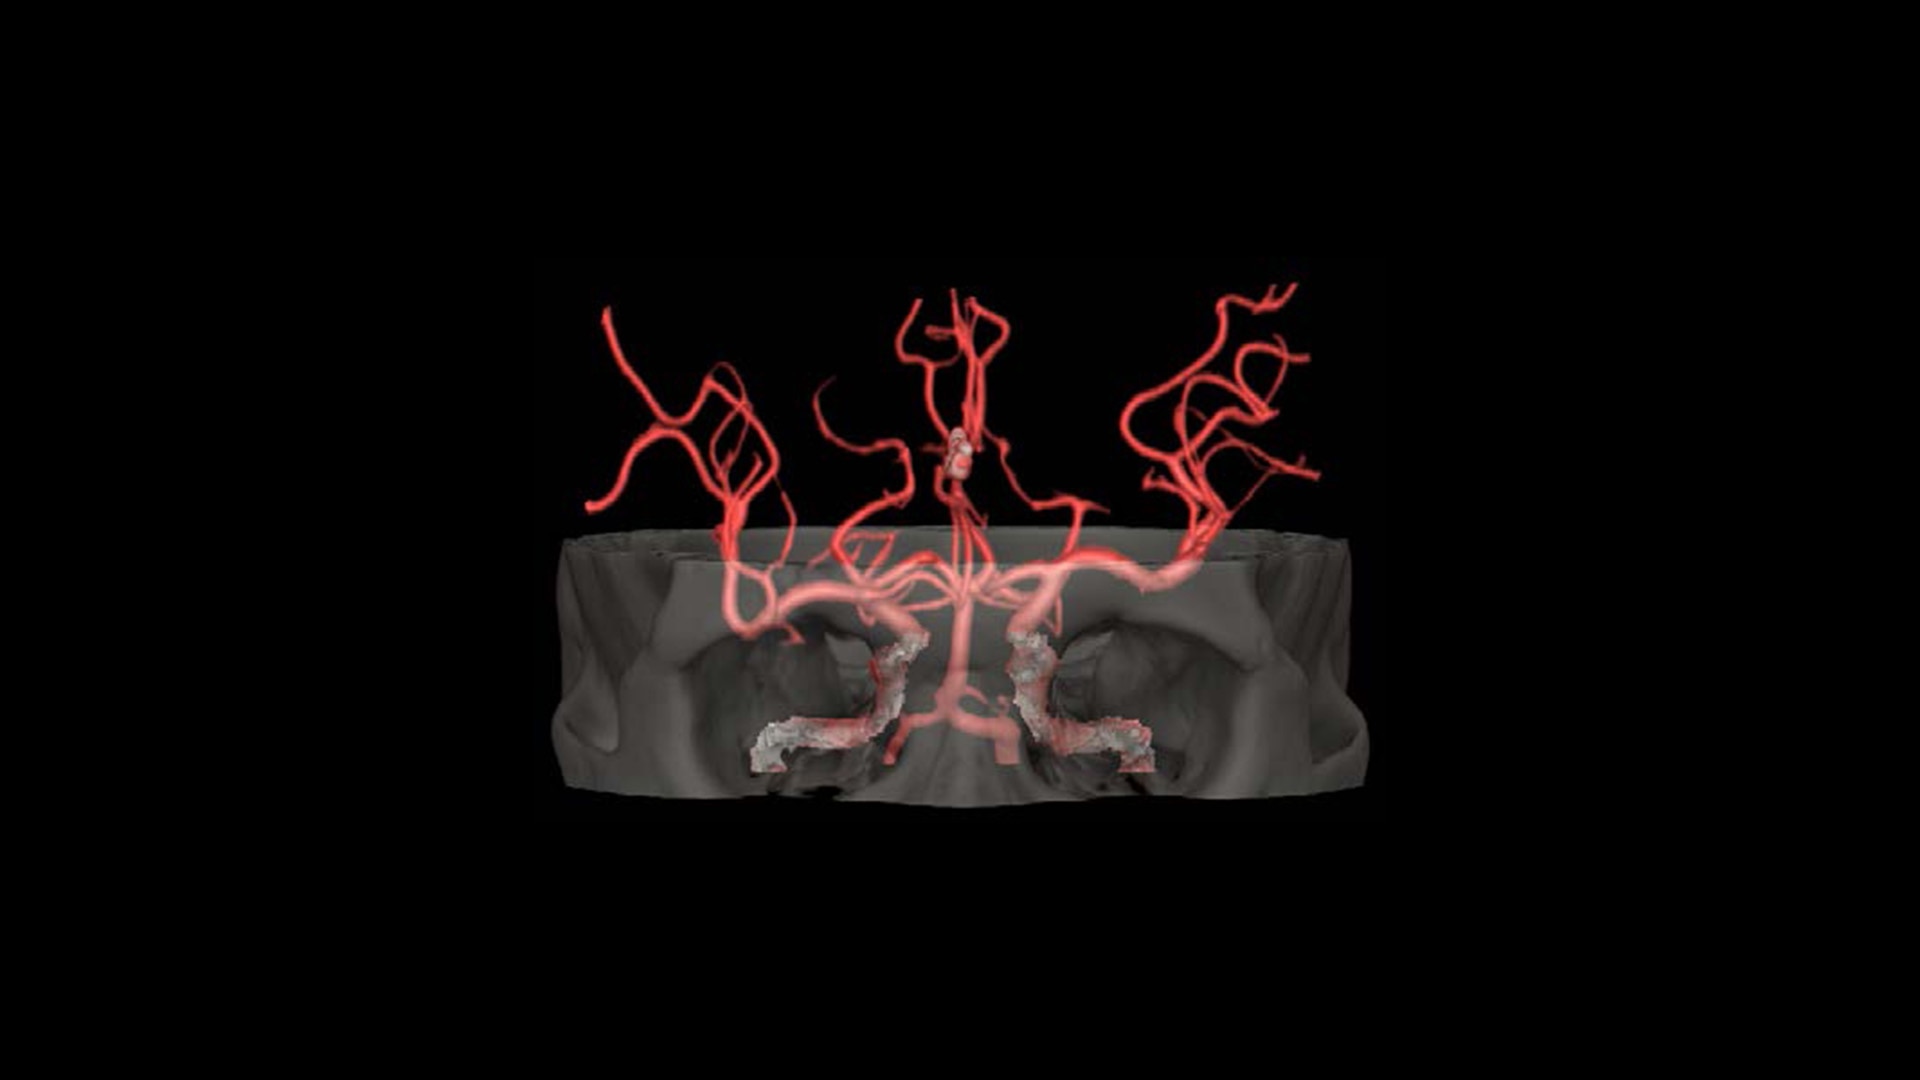

TrueFidelity DL + True Enhance DL

Better together

With the Revolution Ascend Platform, you can combine both of our AI-based imaging reconstruction technologies to create one stunning image. By combining True Enhance DL with TrueFidelity DL, you can achieve images that have less noise, enhanced sharpness and better noise texture than images obtained with ASiR-V.

feature-hero-better-together-dl-desktop